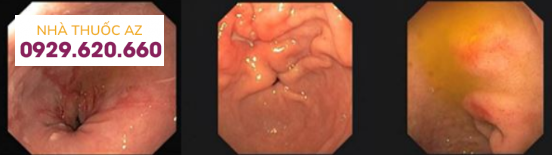

Nội soi tiêu hóa trên cho đến hiện nay là một trong những phương pháp chẩn đoán có độ tin cậy cao nhất giúp phát hiện các bệnh lý của thực quản, dạ dày và tá tràng. Với ưu điểm vượt trội đó, nội soi ngày càng phát triển một cách nhanh chóng với mục tiêu hướng đến là phát hiện những tổn thương nhỏ hơn, ở giai đoạn sớm hơn có khả năng chữa lành hoàn toàn. Ngoài vấn đề còn đọng thức ăn cũ, dịch mật trong ống tiêu hóa, bọt ở đường tiêu hóa trên là một trong những nguyên nhân chính làm trở ngại khi quan sát tổn thương nhỏ này ngay cả khi bệnh nhân đã tuân thủ việc nhịn ăn uống trước cuộc soi.

Hình ảnh niêm mạc đường tiêu hóa trên (thực quản, dạ dày và các bệnh tá tràng) khi nội soi đường tiêu hóa trên

Mặt khác, các bác sĩ nội soi cũng nhận thấy việc cải thiện tốt hơn tình trạng bọt đường tiêu hóa trên đã làm cho hình ảnh nội soi rõ hơn, hỗ trợ cho việc chẩn đoán qua nội soi chính xác, phát hiện các sang thương nhỏ mà trước kia do yếu tố bọt làm che khuất thương tổn, ảnh hưởng đến sự quan sát và đánh giá của Bác sĩ, nhất là tại các vùng mù, vùng khuất như sau tâm vị, sau lỗ môn vị, sau góc bờ cong nhỏ của dạ dày…

Polyp nhỏ ở dạ dày, rất dễ bỏ sót nếu không làm sạch bọt trước nội soi